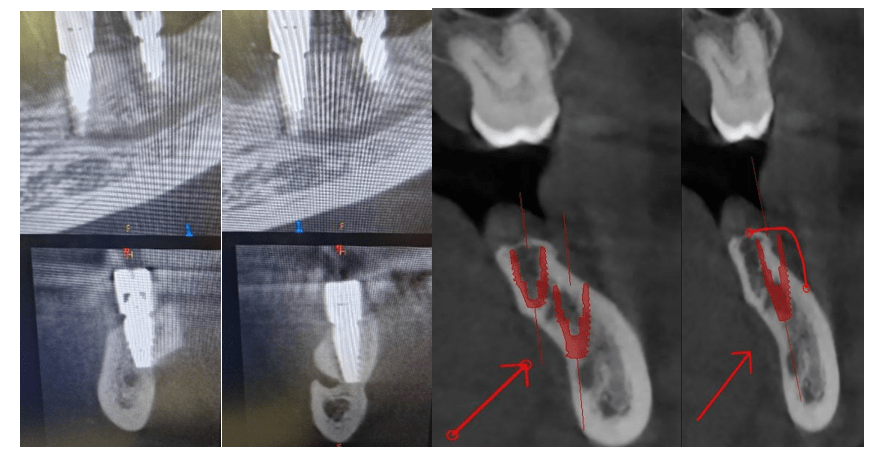

Softver koristi umjetnu inteligenciju, opciju automatskog označavanje mandibularnog kanala. U gotovo 95% slučajeva ova opcija funkcionira besprijekorno, ali naravo uvijek je potrebna kontrola. Softver sam označuje anatomsku liniju presjeka podešenu po donjoj čeljusti što je najčešće dovoljno za plan th, naravno ovo se može odraditi i ručno. Transvezalnu liniju presjeka moguče je naginjati pod željenim kutem što uvelike olakšava planiranje anguliranih implantata.

U prikazu slučaja pokazat ću kako jednostavno planirati. Izabrat ću željeni implantat iz knjižnice softvera te ga virtualno pozicionirati. Najbitnija mi je maximalna dužina implantata kako bi postigao što bolju primarnu stabilnost bikortikalnim sidrenjem a o promjeru implantata odlučujem tijekom zahvata. Također unaprijed planiram nivelaciju kosti.

Iz prikaza slijedećeg slučaja možemo vidjeti da nam 3D prikaz tvrdih tkiva uvelike pomaže za manipulaciju sa mekim tkivima. Točnije sami dizaj režnje uvjetovan je antomskim strukturama koje su vrlo osjetljive te zahtijevaju dodatnu pozornost.

Kod zahtjevnih slučajeva intraoperativan snimak može biti ključan za uspijeh. Na taj način možemo se kontrolirano približiti potencijalno rizičnim antomskim strukturama posebice u donjoj čeljusti bez opasnosti da ih oštetimo. U ovakvim situacijam ključnu ulogu igra iskustvo operatera.